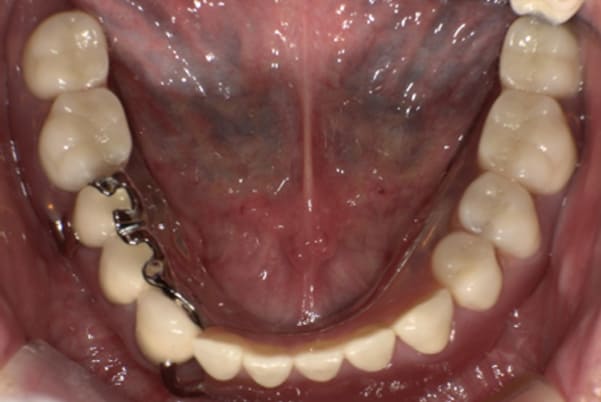

下顎治療前

下顎治療後

治療前の入れ歯の奥歯は、治療後の義歯と比較しても分かるように、歯が削れ平らになった状態です。

これにより奥歯のかみ合わせは低くなり、前歯のみが強くあたり、かみ合わせにより上の前歯大きな負担がかかっていたことにより、上の前歯が折れたことが考えられます。

精密な型どりは、通常保険治療では使用しない、この患者様だけに合った型を取るトレーを作製、また寸法変化の最も少ない精密なシリコンを用いてお口の中を精密に限りなく再現する型どりの方法で型をお取りしました。

完成前に適合や見た目のチェックでは、咬む力で義歯がたわみ、残りの歯に負担がかからないよう、見えない内側は、金属を用い、強度を増し、また金属のため薄くすることで違和感をなくす設計とし、完成前に試し合わせを行い、装着感、審美性を確認しました。

治療用入れ歯は患者様とご相談し、早急にお痛みをとり、お食事ができることをご希望されていたため、歯を抜くと同時に仮の入れ歯が入りお食事をされた後のお写真です。直ちに、お痛みを取り除き、お食事ができるような治療計画としました。

精密義歯は、歯をぬいたあと歯肉が治ってから、精密な入れ歯を作製しました。治療中も、仮の入れ歯があるため、普段の生活に支障がなく、また仮の入れ歯を実際使ってのご意見、ご希望(バネが気になる)をお聞きした上で、精密な義歯に、ご希望を反映し作製しました。

従来の方法では、歯を抜いてから入れ歯を作るまでは、歯茎の治りを待つため数か月かかりますが、患者様のご希望で、見た目、食べることに支障が出ないよう、抜歯と同時に入れ歯を装着し、歯がない期間がない入れ歯を作製したため、その日から、お食事や外出が可能となりました。

また、当然ではありますが、患者様も残りの歯をこれ以上失いたくないとのご希望が強く可能な限り、残りの歯に負担がかからない機能性を重視し、また、バネがなるべく見えない設計とし、機能と審美の両方に重きをおいた入れ歯を作製し、お痛みなく、お食事も召し上がられるようになりました。